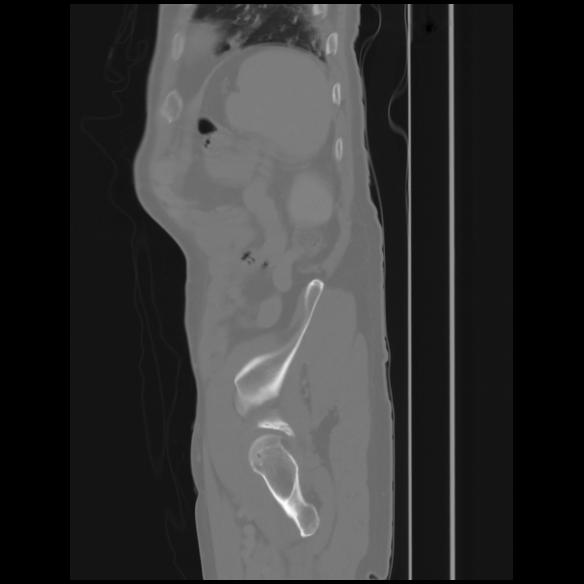

7 CUERPO,CE,Sagittal,3.000,CUERPO,Sagittal,